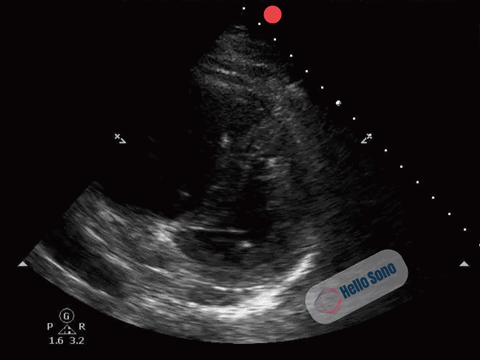

The PSSA view demonstrates a flattened interventricular septum, creating a D-shaped left ventricle instead of the normal circular contour.

In addition, the right ventricle (RV) appears enlarged relative to the left ventricle on this view. The RV cavity occupies a larger proportion of the image than expected.

The combination of RV enlargement and septal flattening reflects acute right ventricular pressure overload.

In the appropriate clinical context, these findings are highly concerning for acute PE.